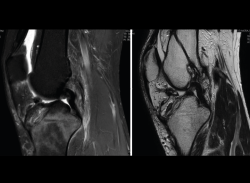

1.2.2. Ligamento cruzado anterior (LCA) (Figuras 40, 41, 42, 43 y 44)

Figura 40. Corte de secuencia sagital T2 Fat-Sat de resonancia magnética de rodilla: ligamento cruzado anterior normal.

Figura 41. Cortes de secuencia sagital T2 Fat-Sat de resonancia magnética de rodilla: rotura central del ligamento cruzado anterior.

Figura 42. Cortes de secuencia sagital T2 Fat-Sat: rotura proximal del ligamento cruzado anterior.

Figura 43. Corte sagital oblicuo T2 de resonancia magnética de rodilla: plastia del ligamento cruzado anterior íntegra.

Figura 44. Corte de secuencia sagital T2 Fat-Sat y T2 de resonancia magnética de rodilla: rotura de plastia del LCA.